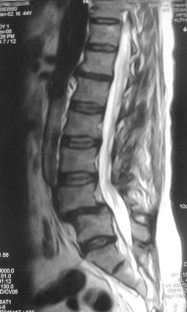

We report a case of L4–L5 traumatic anterolisthesis. The patient was treated surgically 4 months after the injury. His radiological and operative findings showed L4 inferior facet tip fracture, L4–L5 anterior displacement and left L4–L5 foraminal disc protrusion. Decompression, reduction with L3, L4, L5 pedicular screw fixation, L4–L5 disc excision and interbody cage insertion with autologous bone grafts were done. Flexion type injury was thought to be the probable mechanism.

Fig. 4